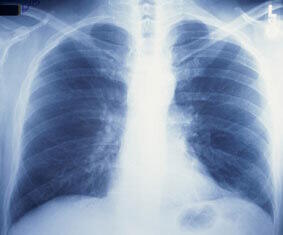

Vitamine C et respiration

Des chercheurs du Children's Hospital & Research Center d'Oakland, en Californie, ont testé l'effet de la vitamine C comme agent de traitement complémentaire de l'asthme, de la mucoviscidose et du syndrome respiratoire obstructif. Ils ont examiné son action sur une protéine appelée régulateur de la conductance transmembranaire de la mucoviscidose (CFTR, cystic fibrosis transmembrane conductance regulator) qui régule les sécrétions de fluide dans les parois des voies respiratoires.

La vitamine C induit une ouverture des canaux du CFTR et une meilleure exposition des parois des voies respiratoires à la vitamine C qui stimule la production de fluide. Les chercheurs ont dit que la vitamine C favorise une hydratation normale des parois des voies respiratoires et que des déficiences en vitamine C pourraient conduire à l'adhésion du mucus sur les membranes tapissant les voies respiratoires.

Lorsque les voies respiratoires ne sont pas suffisamment hydratées, elles deviennent sensibles aux infections susceptibles de provoquer des crises d'asthme chez les asthmatiques.